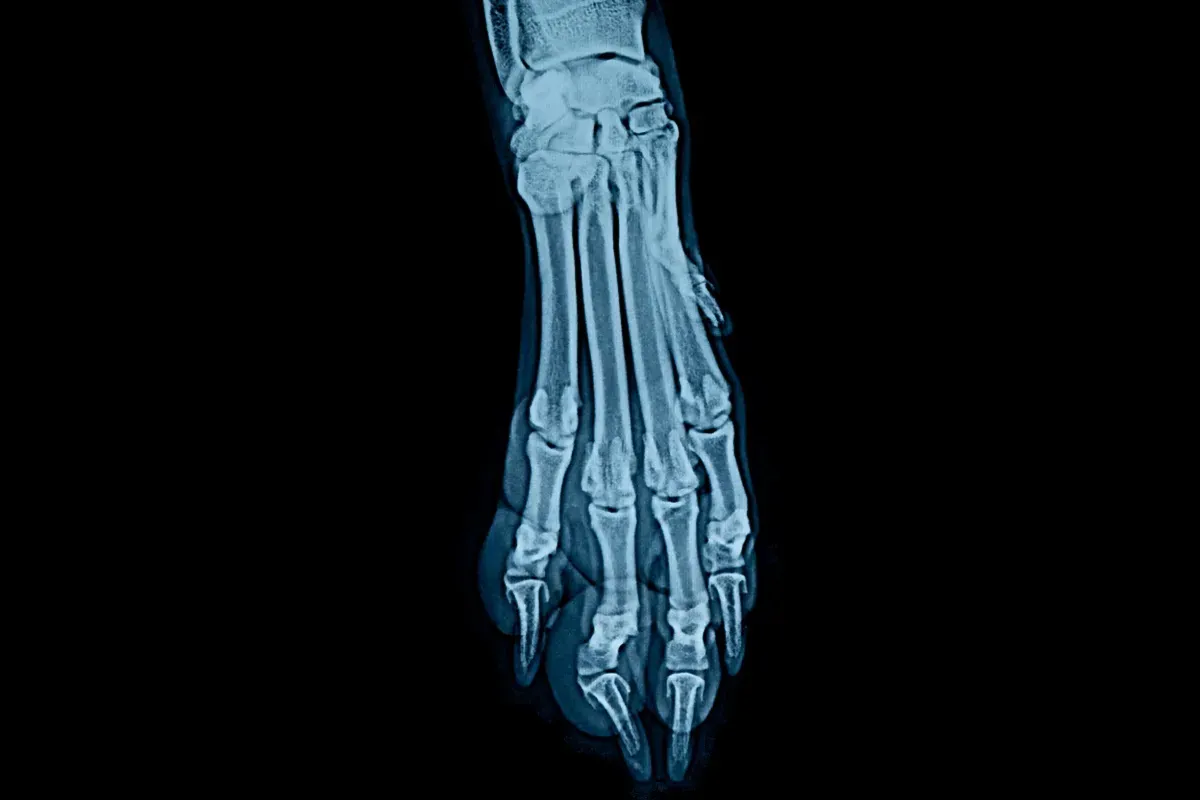

Jak już wspomniałem, w przypadku szczeniąt ras olbrzymich, nadmierna podaż wapnia jest znacznie większym zagrożeniem niż jego niewielki niedobór. Konsekwencje takiego stanu mogą być naprawdę poważne i niestety często nieodwracalne. Do najczęściej występujących schorzeń związanych z nadmiarem wapnia należą: osteochondroza (OCD), czyli zaburzenie tworzenia chrząstki stawowej, które prowadzi do jej oddzielania się od kości, powodując ból i kulawiznę; chondrodystrofia, czyli ogólne zaburzenia rozwoju chrząstki; oraz hiperkalcemia, czyli zbyt wysoki poziom wapnia we krwi, który może prowadzić do uszkodzenia nerek i innych narządów. Ponadto, nadmiar wapnia może wywoływać zaburzenia wzrostu kośćca, które na pierwszy rzut oka mogą przypominać krzywicę, choć ich przyczyna jest zupełnie inna. Co więcej, zbyt wysoki poziom wapnia w diecie może utrudniać wchłanianie innych ważnych minerałów, takich jak cynk, co prowadzi do dalszych niedoborów. Szczególnie wrażliwe na nadmiar wapnia są rasy takie jak dogi niemieckie, u których obserwuje się zwiększoną predyspozycję do tych problemów. Pamiętajmy, że nadmiar wapnia jest głównym żywieniowym czynnikiem ryzyka tych wszystkich chorób wzrostowych.

Z drugiej strony, niebezpieczny jest również niedobór wapnia lub sytuacja, w której stosunek Ca:P jest odwrócony, czyli fosforu jest znacznie więcej niż wapnia. Najbardziej klasycznym przykładem takiej sytuacji jest dieta oparta wyłącznie na mięsie, które jest bogate w fosfor, ale ubogie w wapń. W takim przypadku organizm szczenięcia, aby utrzymać niezbędny poziom wapnia we krwi (który jest kluczowy dla życia), zaczyna "wyciągać" go z kości. Ten proces prowadzi do demineralizacji kości, czyniąc je słabymi i kruchymi. Skutkiem tego jest wtórna żywieniowa nadczynność przytarczyc, gdzie gruczoły te nadmiernie pracują, próbując wyrównać niedobór wapnia kosztem kośćca. Osłabione kości są bardziej podatne na złamania, nawet przy niewielkich urazach, a także mogą prowadzić do poważnych chorób przyzębia. Widziałem szczenięta, u których z powodu źle zbilansowanej diety dochodziło do spontanicznych złamań, co jest dramatycznym przykładem tego, jak ważne są prawidłowe proporcje minerałów.